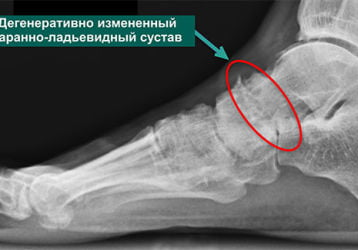

Таранно-ладьевидный сустав: причины артроза, признаки и лечение

Таранно-пяточно-ладьевидный сустав, заболевания, способы лечения артроза. Медикаменты и хирургия, упражнения и реабилитация.